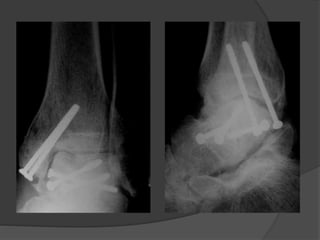

TRATAMIENTO

 Reducción abierta

 Artrodesis subastragalina primaria

 talectomía

Abordaje anteromedial.

 Asociado a Fx.maleolo medial.

 Osteotomia maleolar medial(Chevron)

 Resultados insatisfactorios en 90%

 Necrosis avascular 69 al 100%

 Consolidación viciosa 32 al 54%

 Retardo de consolidación 21%

 Pseudoartrosis 12%

 Artritis degenerativa 70%